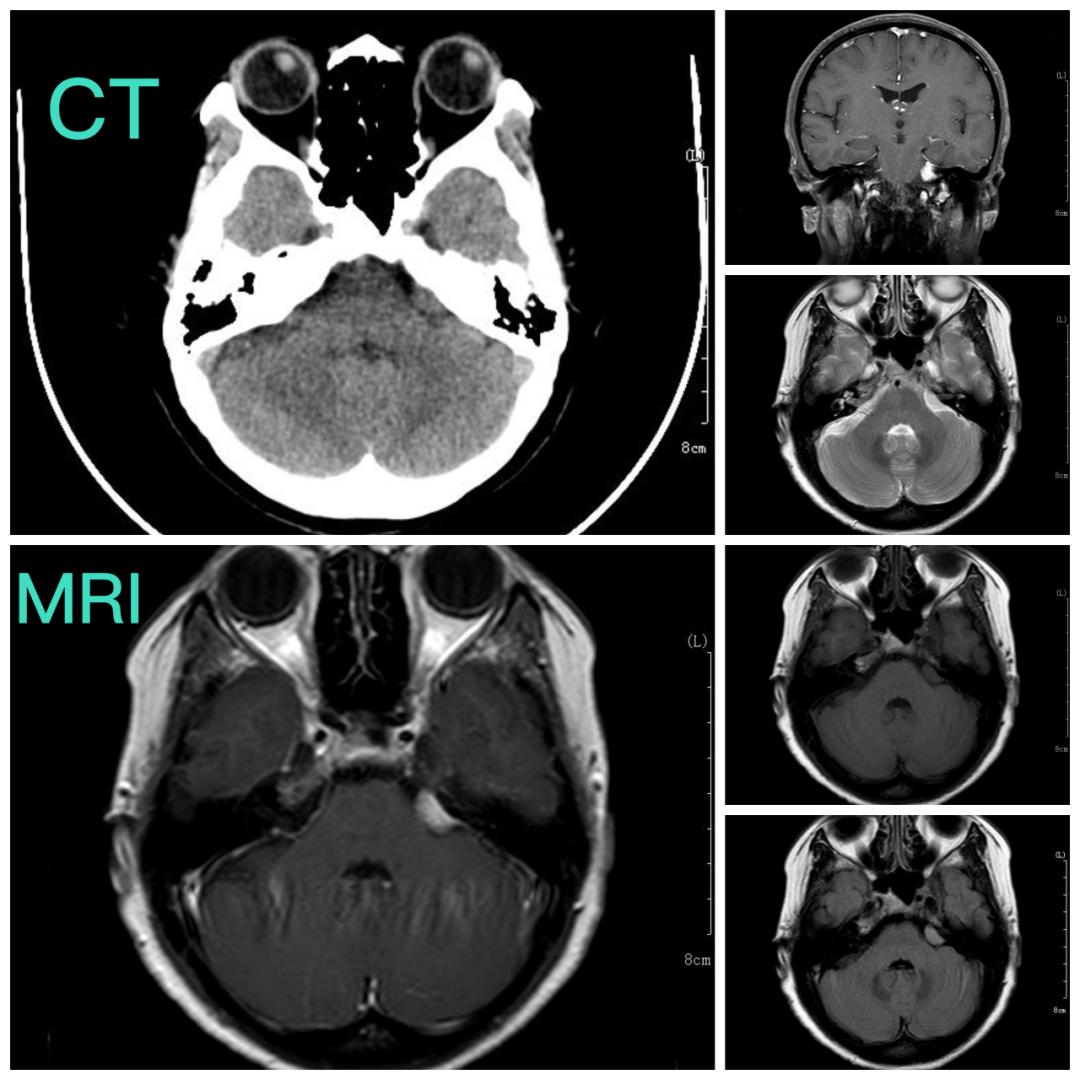

术前影像资料

张永力院长、神外二病区杨海峰主任、主治医师段磊认真询问患者病史及仔细查看患者影像资料,考虑肿瘤是脑膜瘤,位于左侧岩骨后壁,位置毗邻脑干和小脑,这个区域有很多脑神经出入,非常凶险,万幸的是肿瘤还比较小,需要尽早手术切除,以免肿瘤长大,增大手术难度,破坏脑干、小脑及脑神经功能,导致无法挽回的损伤。

患者目前右面部的麻木症状,考虑与脑瘤无明显关系,手术无法缓解右面部麻木症状,术后患者头痛症状可能会缓解,最重要的是可以完全切除肿瘤,避免以后对患者导致生命威胁。通过核磁共振影像,可以看出,肿瘤位于左侧岩骨后壁,与面听神经关系最为紧密,肿瘤虽小,但位置较深,经过术前讨论与研判,杨海峰主任认为,手术方式可以选择经神经内镜切除肿瘤,充分发挥神经内镜的优势,微创切口,深入抵达肿瘤所在部位,视野清晰,操作精准,在完整切除肿瘤的同时,完整保护面听神经及脑干、小脑等重要的结构。